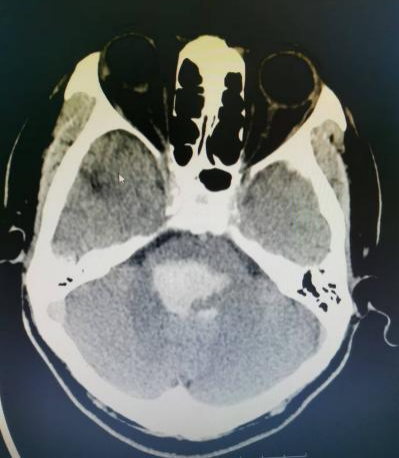

7月下旬的一天,正在开会的李老师突然意识不清伴恶心、呕吐不适,四肢僵直、小便失禁,于是呼叫“120”由我院急诊人员接回,行颅脑CT后提示脑干出血(脑桥出血伴脑内血肿)。

神经外科主治医师唐清明阅片后,诊断患者脑干血肿及呼吸衰竭明确,随时可能呼吸、心跳停止死亡,目前仅脑干血肿清除手术可能有机会挽救患者生命。

脑干出血既往属于神经外科手术禁区,但近年来随着神经外科设备的更新以及技术的飞速发展,我院神经外科团队不懈努力,目前已经熟练掌握此项手术技术。全院各科室争分夺秒,在李老师入院40分钟内其送入手术室,征得家属同意后,唐清明在显微镜下精细手术操作,历经2小时30分钟成功完成手术,术后复查CT提示脑干区血肿清除。术后1周患者恢复自主意识,目前正在康复过程中。